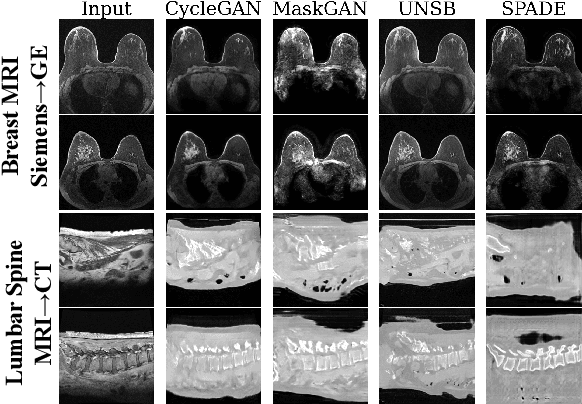

Abstract:Modern medical image translation methods use generative models for tasks such as the conversion of CT images to MRI. Evaluating these methods typically relies on some chosen downstream task in the target domain, such as segmentation. On the other hand, task-agnostic metrics are attractive, such as the network feature-based perceptual metrics (e.g., FID) that are common to image translation in general computer vision. In this paper, we investigate evaluation metrics for medical image translation on two medical image translation tasks (GE breast MRI to Siemens breast MRI and lumbar spine MRI to CT), tested on various state-of-the-art translation methods. We show that perceptual metrics do not generally correlate with segmentation metrics due to them extending poorly to the anatomical constraints of this sub-field, with FID being especially inconsistent. However, we find that the lesser-used pixel-level SWD metric may be useful for subtle intra-modality translation. Our results demonstrate the need for further research into helpful metrics for medical image translation.